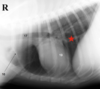

Is the circled lesion more likely in the lung or the mediastinum?

Lung

Note the acute angle to the body wall. If the lesion was in the lung you would not have such an acute angle